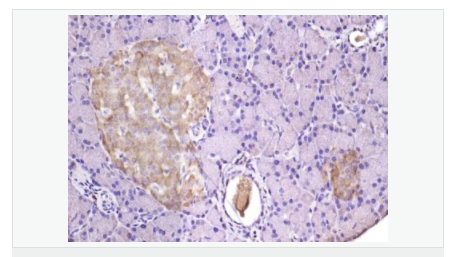

| 產(chǎn)品應用 | WB=1:500-2000 ELISA=1:5000-10000 IHC-P=1:100-500 IHC-F=1:100-500 IF=1:100-500 (石蠟切片需做抗原修復) not yet tested in other applications. optimal dilutions/concentrations should be determined by the end user. |

| 細胞定位 | 細胞漿 細胞膜 |

| 產(chǎn)品介紹 | TMED4 is a putative NF-kB activating protein belonging to the EMP24/GP25L family, and contains 1 GOLD domain. It is also known as Transmembrane emp24 protein transport domain containing 4. Function: Involved in vesicular protein trafficking, mainly in the early secretory pathway. targeting. Involved in the maintenance of the Golgi apparatus. Appears to play a role in the biosynthesis of secreted cargo including processing. Involved in endoplasmic reticulum stress response. May play a role in the regulation of heat-shock response and apoptosis Subcellular Location: Endoplasmic reticulum membrane; Single-pass type I membrane protein Similarity: Belongs to the EMP24/GP25L family. Contains 1 GOLD domain. SWISS: Q7Z7H5 Gene ID: 222068 Database links: Entrez Gene: 222068 Human Entrez Gene: 103694 Mouse Omim: 612038 Human SwissProt: Q7Z7H5 Human SwissProt: Q8R1V4 Mouse Unigene: 598832 Human Unigene: 715273 Human Unigene: 254495 Mouse Important Note: This product as supplied is intended for research use only, not for use in human, therapeutic or diagnostic applications. |